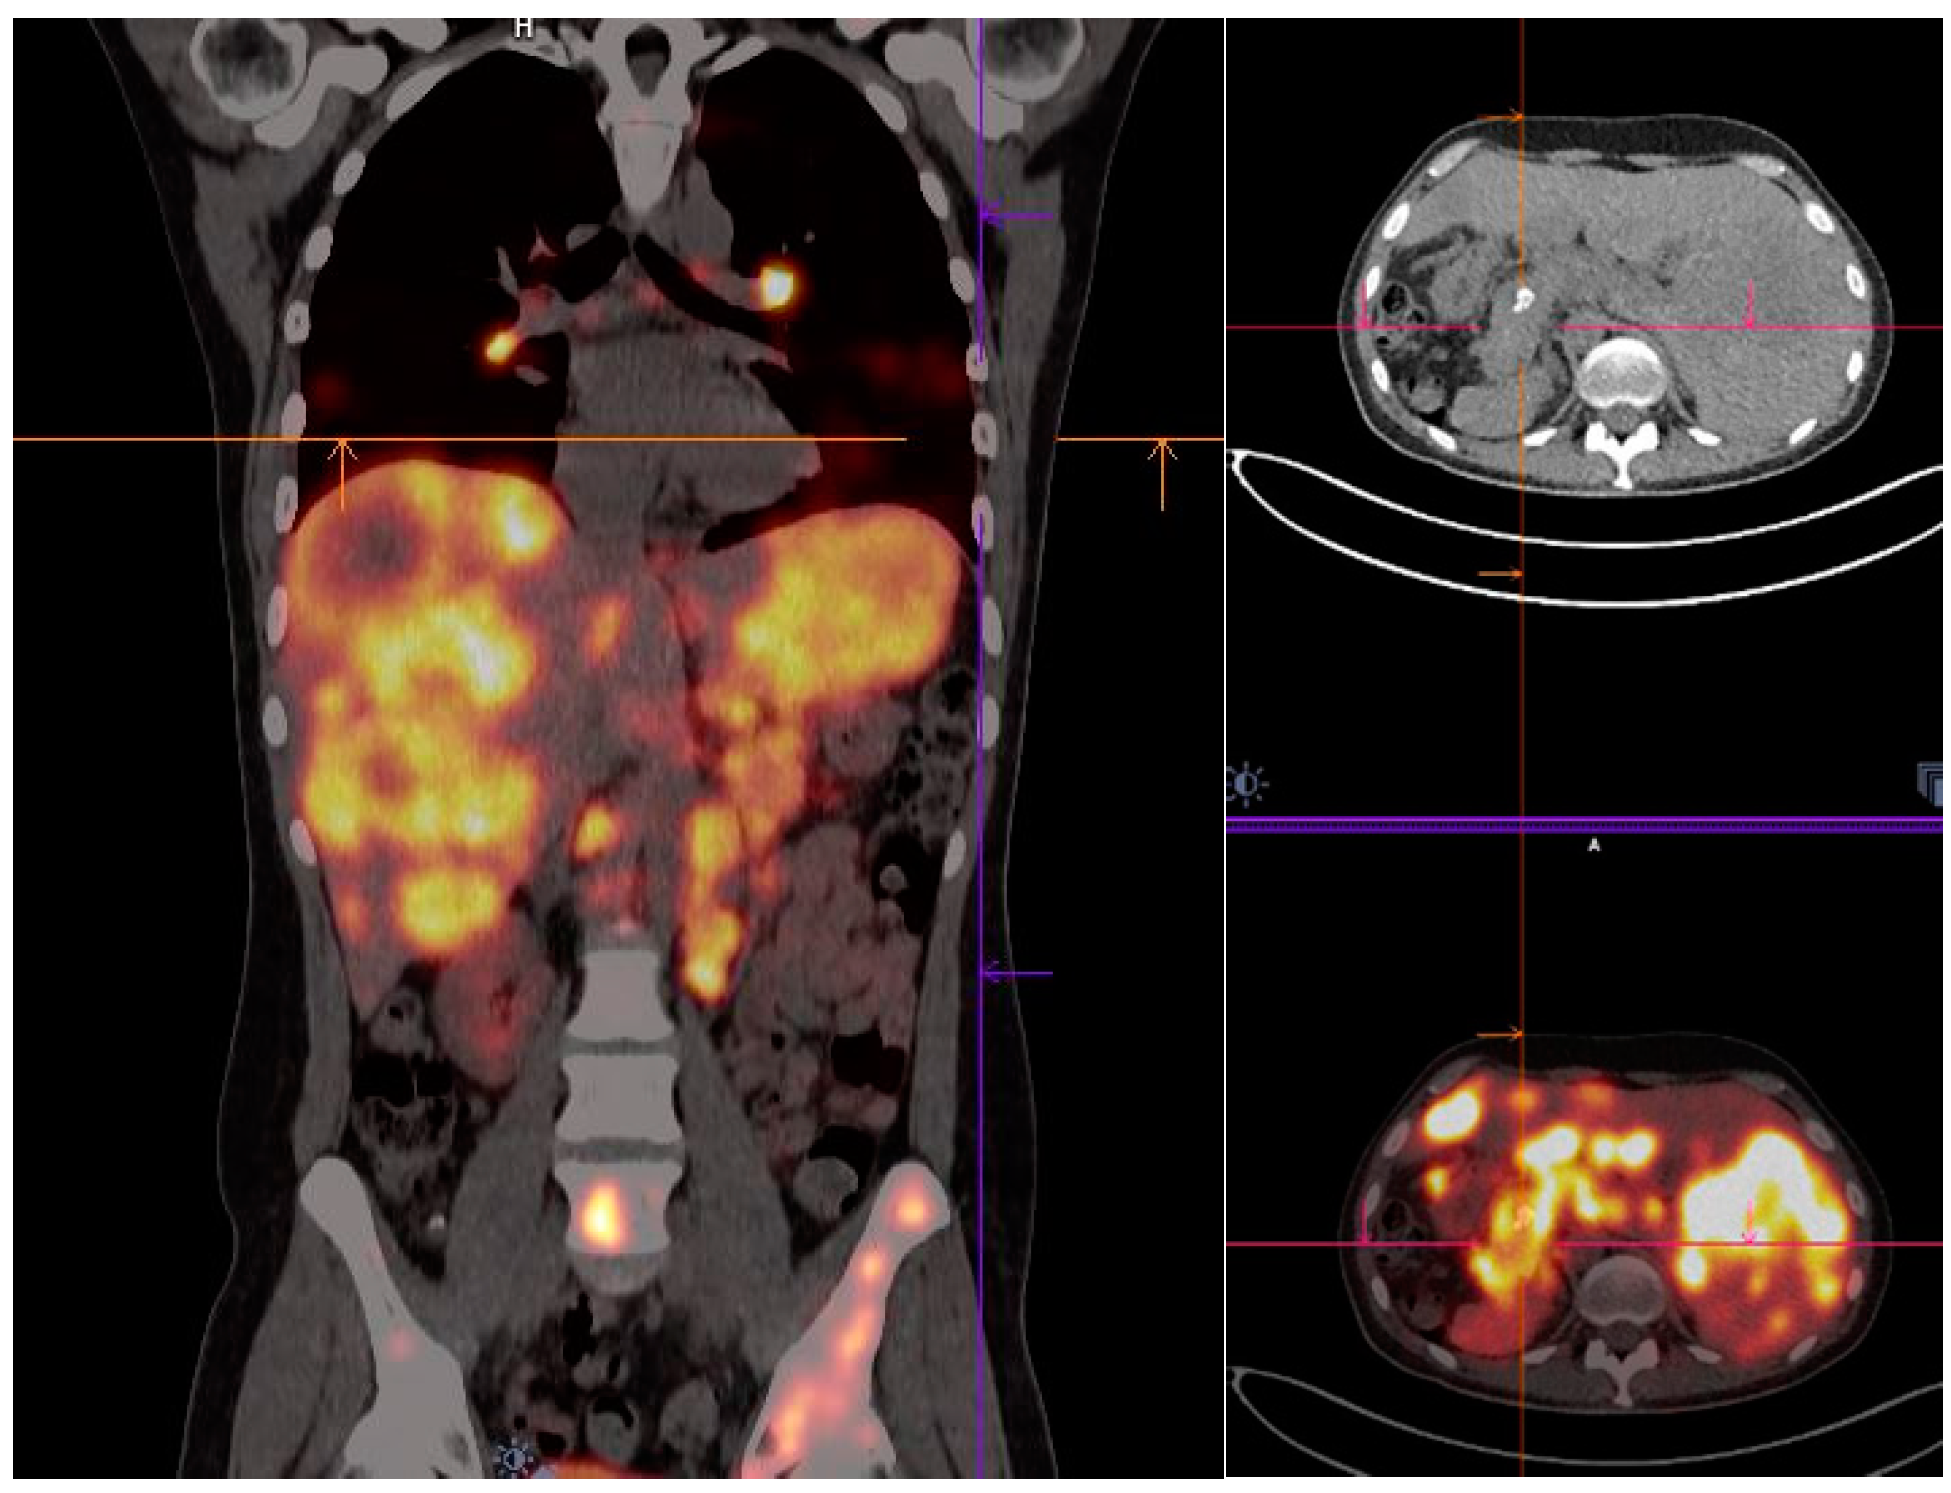

- Mirzaei, S.; Revheim, M.-E.; Raynor, W.; Zehetner, W.; Knoll, P.; Zandieh, S.; Alavi, A. 64Cu-DOTATOC PET-CT in patients with neuroendocrine tumors. Oncol. Ther. 2020, 8, 125–131. [Google Scholar] [CrossRef]

- Carlsen, E.A.; Johnbeck, C.B.; Binderup, T.; Loft, M.; Pfeifer, A.; Mortensen, J.; Oturai, P.; Loft, A.; Berthelsen, A.K.; Langer, S.W. 64Cu-DOTATATE PET/CT and prediction of overall and progression-free survival in patients with neuroendocrine neoplasms. J. Nucl. Med. 2020, 61, 1491–1497. [Google Scholar] [CrossRef]

- Pfeifer, A.; Knigge, U.; Mortensen, J.; Oturai, P.; Berthelsen, A.K.; Loft, A.; Binderup, T.; Rasmussen, P.; Elema, D.; Klausen, T.L. Clinical PET of neuroendocrine tumors using 64Cu-DOTATATE: First-in-humans study. J. Nucl. Med. 2012, 53, 1207–1215. [Google Scholar] [CrossRef]

- Delpassand, E.S.; Ranganathan, D.; Wagh, N.; Shafie, A.; Gaber, A.; Abbasi, A.; Kjaer, A.; Tworowska, I.; Núñez, R. 64Cu-DOTATATE PET/CT for imaging patients with known or suspected somatostatin receptor–positive neuroendocrine tumors: Results of the first US prospective, reader-masked clinical trial. J. Nucl. Med. 2020, 61, 890–896. [Google Scholar] [CrossRef]

- Loft, M.; Carlsen, E.A.; Johnbeck, C.B.; Johannesen, H.H.; Binderup, T.; Pfeifer, A.; Mortensen, J.; Oturai, P.; Loft, A.; Berthelsen, A.K. 64Cu-DOTATATE PET in patients with neuroendocrine neoplasms: Prospective, head-to-head comparison of imaging at 1 hour and 3 hours after injection. J. Nucl. Med. 2021, 62, 73–80. [Google Scholar] [CrossRef] [PubMed]

| [64Cu]Cu-DOTA-TOC | NET | 33 | 2019 | High detection rate and high target to background ratio in images raised [64Cu]Cu- DOTA-TATE as a promising and safe radiolabeled SST derivative for NET detection | [22] |